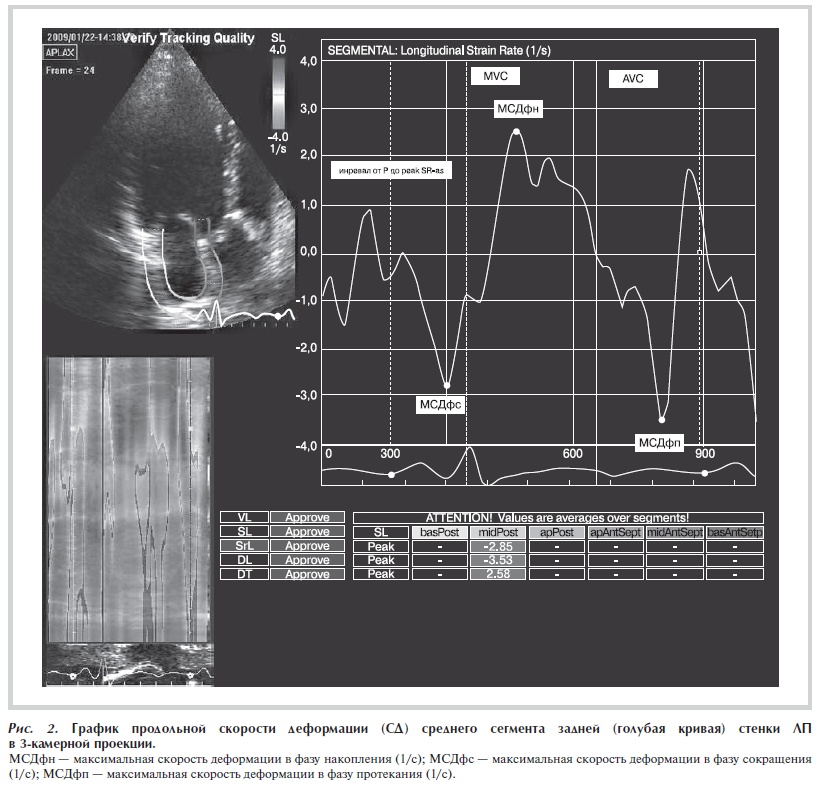

Рисунок 1. График продольной деформации (Д) средних сегментов нижней (голубая кривая) и передней (синяя кривая) стенок ЛП в 2 камерной проекции.

анализа. В результате анализа программа выстраивает графики продольной деформации и продольной скорости деформации выбранных оператором сегментов предсердия. На рис. 1 и 2 приведены примеры графиков кривых деформации и скорости деформации миокарда ЛП. На полученных графиках проводились измерения деформации и скорости деформации в разные фазы

сердечного цикла. Максимальная продольная деформация была измерена в фазу сокращения (МДфс, %), соответствующую систоле предсердий, от начала зубца Р на ЭКГ до закрытия МК (MVC) и в фазу накопления (МДфн, %), соответствующую систоле желудочков, от закрытия МК до закрытия аортального клапана (AVC). В фазу протекания измерение максимальной деформации не проводилось. Это связано с полученными результатами предыдущей работы, в которой были обследованы здоровые лица [8]. В этом исследовании было продемонстрировано, что в фазу протекания у 50% обследованных здоровых лиц показатели максимальной деформации были равны 0 независимо от сегмента, позиции и качества визуализации. Это связано с отсутствием пика деформации миокарда в указанный период. Деформация в эту фазу переходит из одного пика (максимального удлинения) в другой пик (максимального укорочения) в фазу сокращения. Как известно, в фазу протекания предсердие является пассивным проводником для переноса крови и миокард практически не смещается. Максимальная скорость деформации была измерена в фазу сокращения (МСДфс, 1/s), в фазу накопления (МСДфн, 1/s) и в фазу протекания предсердий (МСДфп, 1/s), соответствующую периоду раннего наполнения ЛЖ с момента открытия МК (MVO) до зубца Р на ЭКГ. МСД и МД рассчитывали для следующих сегментов ЛП: а) в 4-камерной верхушечной позиции для средних сегментов боковой стенки ЛП и ПП, перегородки предсердий; б) в 3-камерной верхушечной позиции для средних сегментов задней стенки ЛП; в) в 2-камерной верхушечной позиции для средних сегментов нижней стенки ЛП и передней стенки ЛП.